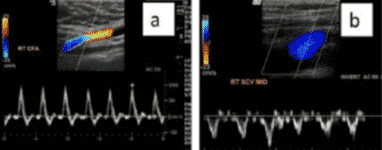

En el caso de existir dudas, el método más fiable para diferenciarlas seria la realización de un Doppler pulsado donde las venas se representan como una onda bifásica y a veces una retrograda de baja velocidad; mientras que la arteria presenta un flujo fundamentalmente sistólico de alta velocidad.

En lo que a la técnica se refiere, también se utiliza la sonda lineal de alta frecuencia. En este caso es preferible el uso de Doppler a color, útil también para determinar permeabilidad, aunque también puede emplearse el modo 2D.

La ventaja de contar con Doppler a color es que este modo aporta información sobre la existencia y movimiento del flujo sanguíneo, siendo posible localizar regiones con flujo anormal. Queda representado de la siguiente forma:

- Color rojo: flujo que se acerca al transductor.

- Color azul: flujo que se aleja del transductor.

En la detección de trombos se puede observar una imagen ecogénica heterogénea que ocupa total o parcialmente la luz venosa y se considera un signo prácticamente patognomónico la imposibilidad de comprimir la luz vascular por completo. Además, si utilizamos Doppler a color aplicado sobre la luz vascular se apreciará ausencia de flujo o algún defecto de repleción.